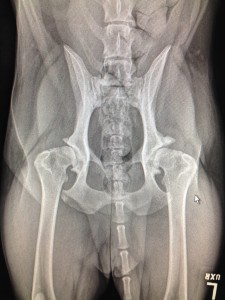

Voici ici des hanches normales. Les têtes fémorales sont bien rondes et entrées profondément dans l’articulation. L’espace articulaire est bien égal indiquant une bonne congruence. Les rebords osseux sont lisses, indiquant l’absence d’ostéoarthrose.